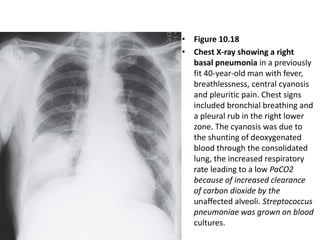

• Figure 10.18

• Chest X-ray showing a right

basal pneumonia in a previously

fit 40-year-old man with fever,

breathlessness, central cyanosis

and pleuritic pain. Chest signs

included bronchial breathing and

a pleural rub in the right lower

zone. The cyanosis was due to

the shunting of deoxygenated

blood through the consolidated

lung, the increased respiratory

rate leading to a low PaCO2

because of increased clearance

of carbon dioxide by the

unaffected alveoli. Streptococcus

pneumoniae was grown on blood

cultures.